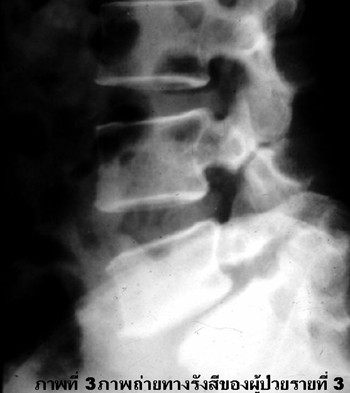

ชายไทยคู่อายุ 45 ปี รู้สึกปวดหลังมานาน 2 ปี ปวดมากขึ้นเรื่อยๆ โดยเฉพาะเวลายกของหนัก. ผู้ป่วยทำงานยกของหนัก. 1 เดือนมานี้อาการปวดรุนแรงมากขึ้นเรื่อยๆ. การตรวจทางรังสีปรากฏดังภาพที่ 3.

1. Plain film lateral L-S spinal.

2. Spondylolysis ของ L4, L5 ร่วมกับ spondylolisthesis ระดับที่ 1 บริเวณ L5 ต่อกับ S1 และหมอนรองกระดูก L5, S1ตีบแคบ.

3. Spinal canal stenosis จากภาวะ spondylolisthesis ระดับที่ 1 บริเวณ L5 ต่อ S1 ร่วมกับ spondylolysis ของ L5 และหมอนรองกระดูกระดับ L5, S1 แคบ.

4. MRI scan ของ L-S spines หรือ myelogram จะแสดงการกดของ roots และ canal อย่าง ชัดเจน และถ้าตรวจ myelogram อาจตรวจการถ่ายเทของ CSF โดยให้ผู้ป่วยงอและเหยียดหลังแล้ว ประเมินว่า spondylolysis และ spondylolisthesis ของกระดูกสันหลังเพิ่มขึ้นหรือลดลงหรือไม่ อันบ่งชี้ความมั่นคงของ spondylolisthesis.